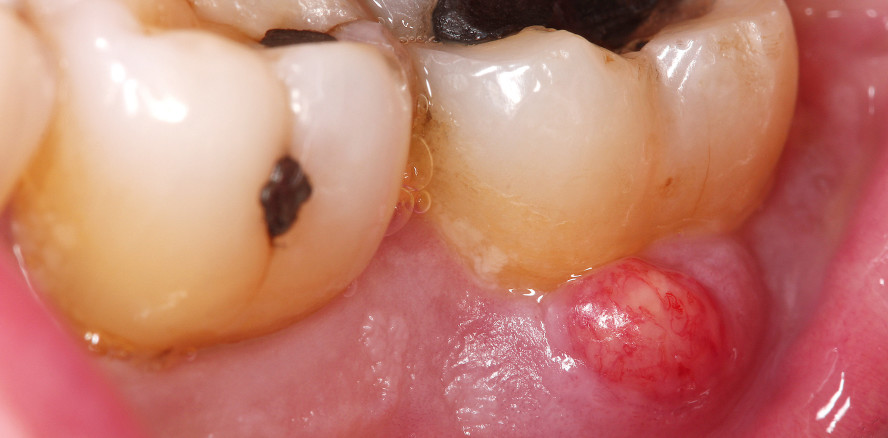

Bei Patienten mit einer schweren Parodontitis und hoher Keimlast mit Taschensekretion oder in Situationen mit nicht erkannter Endo-Paro-Läsion kann es durch eine professionelle Zahnreinigung (PZR) in der Hygienephase zu einer Abszessbildung kommen. Grund hierfür ist, dass es bei einer Reinigung der Zahnoberflächen zu einer spontanen Ausheilung des entzündeten Zahnfleischsaums kommen kann. In diesem Fall werden die Fasern im Zahnfleisch wieder straff, legen sich eng an den Zahn an und bilden dabei eine Art „sealing“. Da durch die Zahnreinigung die Keimlast in den tiefen parodontalen Taschen jedoch nicht reduziert wird, verhindert das abdichtende nun gesunde Zahnfleisch den Ablauf des Taschensekrets. Es kommt zu einer Ansammlung des entzündlichen Sekrets und zur Abszessbildung (Abb. 2a und b). Dies führt zu schmerzhaftem Anschwellen des Zahnfleischs. Es muss daher von dem Zahnarzt bereits im Vorfeld entschieden werden, ob es Sinn macht, in solchen Fällen die Hygienephase vor einer Parodontitistherapie zu überspringen und sofort mit der Parodontitistherapie zu beginnen oder endodontisch tätig zu werden, um das „sealing“ und somit eine Abszessbildung zu verhindern. Kommt es jedoch zu einer Abszedierung, muss die Tasche sofort gereinigt oder in schlimmeren Fällen der Abszess chirurgisch eröffnet werden. In Ausnahmefällen kann zusätzlich eine Antibiose vonnöten sein.4